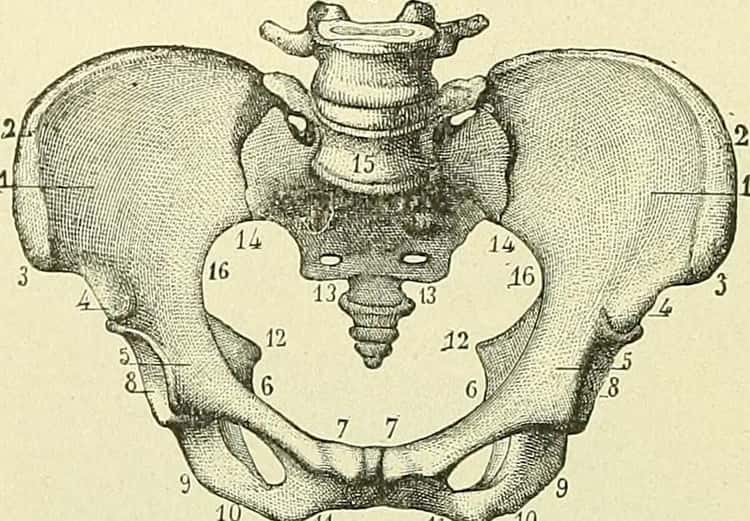

Kostrč

Na základe biologických poznatkov evolúcie vieme povedať, že predkovia ľudí mali chvost. S nasledujúcim vývojom, zmenou prostredia a spôsobu života však prestal byť užitočný. Avšak zostala nám kostrč, ide o dolnú časť chrbtice – tri až päť zrastených stavcov, ktoré sa spájajú s krížovou kosťou.